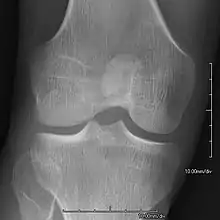

- Patellar involvement is present in approximately 90% of patients; however, patellar aplasia occurs in only 20%.

- In instances in which the patellae are smaller or luxated, the knees may be unstable.